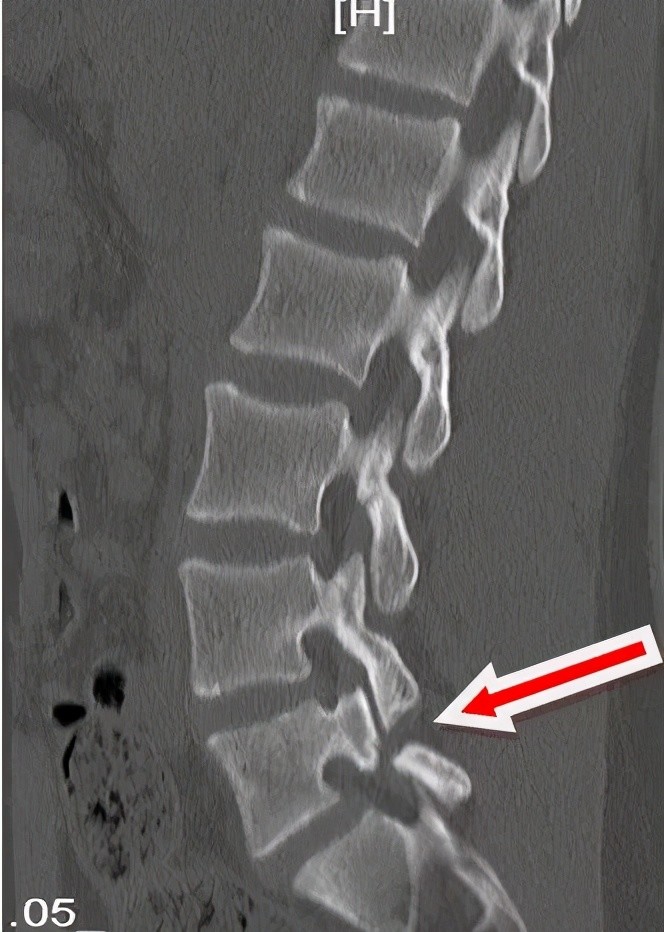

腰椎峡部不连图片

x线,ct提示峡部不连性腰椎滑脱

腰椎峡部裂的影像学_腰椎滑脱_腰椎滑脱检查 - 好大夫在线

腰椎峡部裂1例